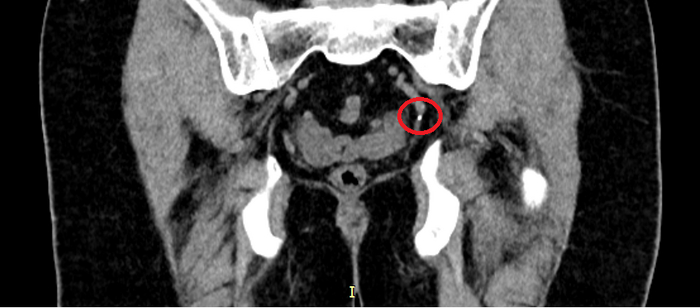

Мазок на инфекции, УЗИ, Сумамед "на всякий случай". Мазок - это тоже больно. Это такой ёршик, который тебе прямо туда засовывают. Но не так больно, как писать. Анализы хорошие, а вот УЗИ... Песочек у меня. Не камни - много мелкой фракции. Видимо что-то покрупнее проскочило наружу, оцарапало мочеточник, воспалилось и теперь болит.

Что делать? Пейте толокнянку по паре столовых ложек в качестве мочегонного. И ждите пока всё выйдет. Потом снова на УЗИ. И я пью. Неделю пью. Две пью. Болит уже не только член. Больно теперь еще и внутри. Иду снова к доктору. Снова УЗИ.

- Всё нормально, - говорит, - песочек пошёл, - говорит, - лоханка расширена и болит. Пейте толокнянку. И брусничный лист. По две столовых ложки. Перестанет болеть - приходите.